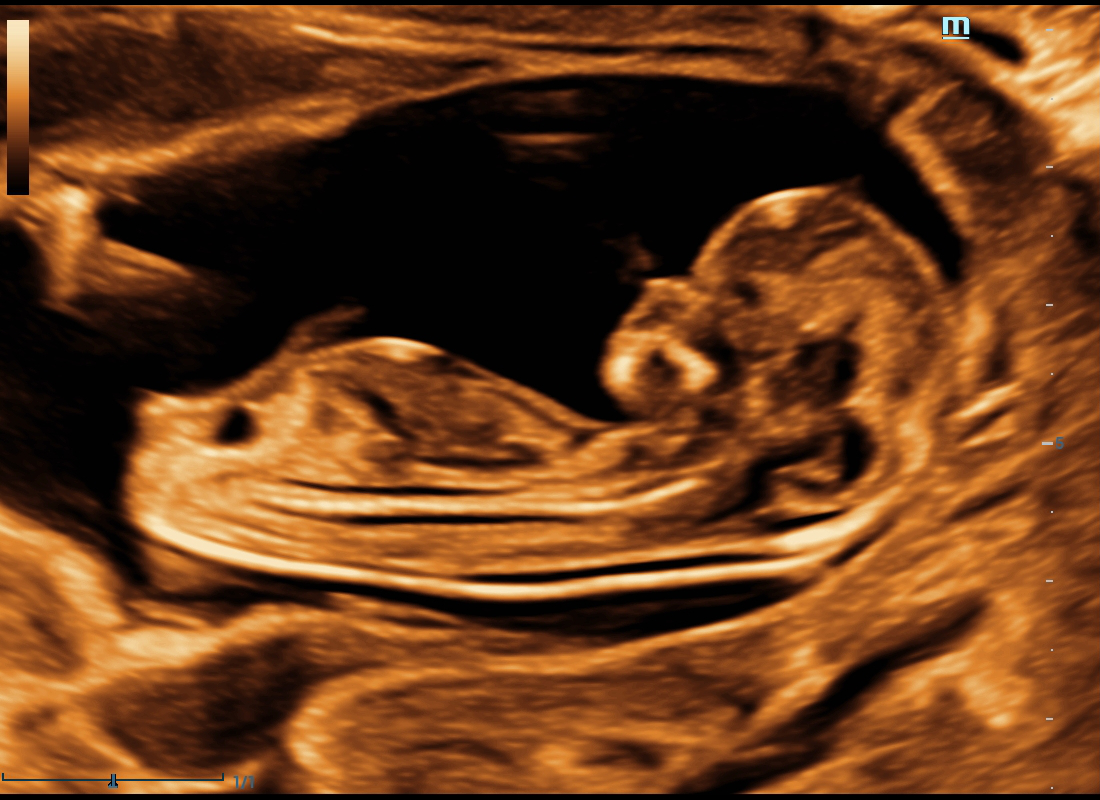

The volume imaging of fetal face is very important for the obstetric doctors whehere they make the face malformation diagnosis or a fully communication with parents. We deeply understand how Nuewa users need more intuitive fetal stereoscopic imaging to help parents quickly establish parent-child links at different gestational weeks.